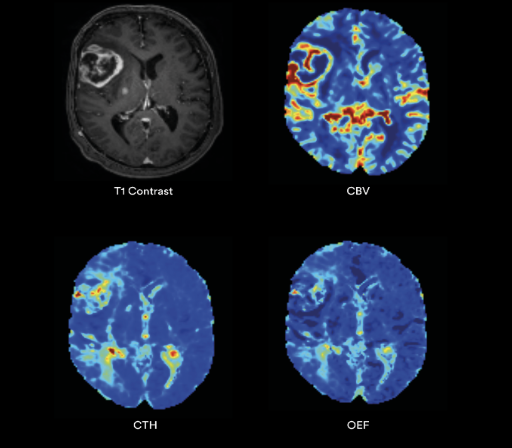

NeuroQuant® Brain Tumor includes tumor segmentations that are color-coded slice by slice and routed to PACS, making it easy for radiologists to identify regions of interest and track changes over time. The integration of Restriction Spectrum Imaging (RSI) provides deeper insights into tumor microstructure, enhancing the analysis with more detailed information than traditional imaging methods.

• High- and low-grade glioma: Slice by slice tumor segmentation in DICOM format

• Longitudinal disease assessment: Automated quantification and tracking of pre- and post-treatment brain tumor volumes across time

• Unique microstructure insights: Patented Restriction Spectrum Imaging (RSI) advanced diffusion technology